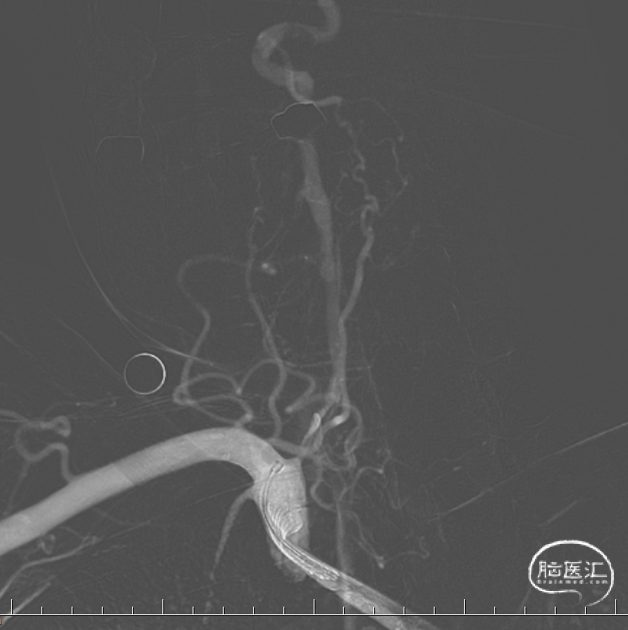

患者平卧位,常规消毒铺巾,局麻下以Seldinger法取右侧股动脉穿刺处,穿刺成功后,置8F股脉鞘。通路建立成功后,进行每公斤体重2/3全身肝素化,用猪尾、单弯导管及高压注射器行脑血管造影术,DSA显示:II型主动脉弓,血管迂曲,双侧锁骨下动脉通畅,右侧椎动脉V1段闭塞,有肌支动脉向V2段注入,V2-V4段可显影,左侧椎动脉V4段纤细,基底动脉及双侧大脑后动脉通畅;双侧颈总动脉及其分支动脉未见明显异常。

因该患者锁骨下动脉成角较大,且直径较为粗大,故采用冠脉6F JR4.0 造影导管,导管改善入路,提供良好支撑,便于微导丝成功通过闭塞段。将JR4.0 造影导管鞘置于右侧锁骨下动脉椎开口处,充分显示椎动脉狭窄部位。

路图指引下,将Pilot150 0.014inch微导丝配合SL-10微导管尝试穿过椎动脉V1段闭塞部位,反复尝试不能通过闭塞段,更换Avigo 0.014inch微导丝,导丝最终成功通过闭塞段,微导管造影证实位于血管真腔,远端血管通常,更换Transend 0.014inch微导丝送至右侧椎动脉V3段,交换出微导管。

沿微导丝送入2.0*20mm 优游球囊于椎动脉狭窄段预扩张,回撤球囊,复查造影提示右侧椎动脉V1段再通,残余长节段狭窄。